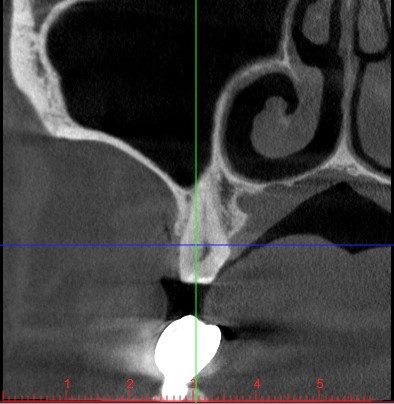

Sì perché, incredibilmente, il collega aveva fatto anche una tac. Guarda, ho fatto uno screenshot:

A parte che penso concordiamo tutti sul fatto che il dente non sia da togliere ma semplicemente da restaurare mantenendone la vitalità ma, ammesso anche che uno volesse proprio toglierlo sono sicuro che il consulente maxillofacciale del collega non avrebbe avuto la minima difficoltà nel posizionare un impianto in seguito.